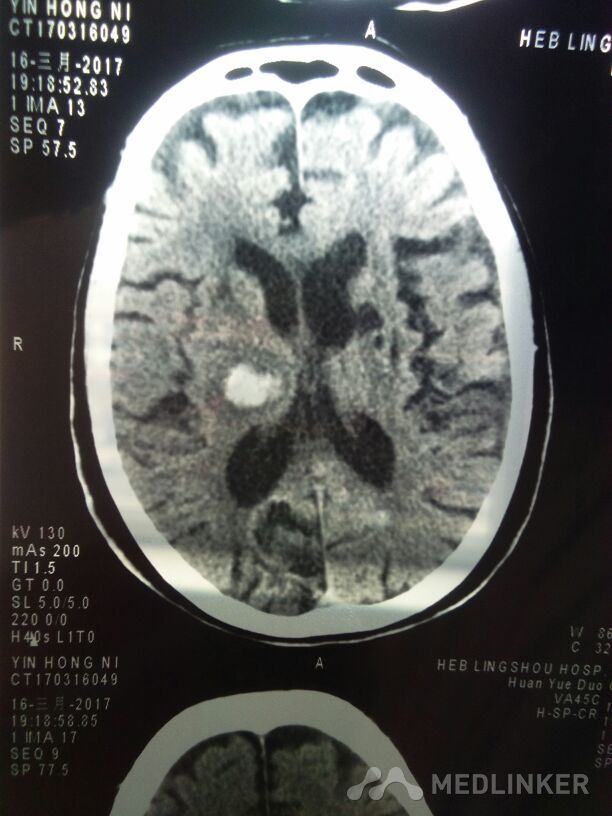

丘脑出血

左侧丘脑出血

脑出血